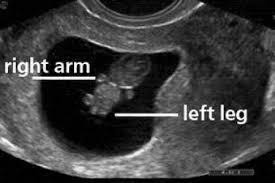

This is what the embryo looks like at 8 weeks. Fingers are well observable on the tiny hands and he periodically tries to make motions with them. Can the fetus actually be 20 weeks along and just look like 8 weeks due to iugr dr. This ultrasound can check the size of the embryo and confirm that there is a heartbeat.

The outer ears would be starting to form. Advanced forms such as 8 week 4d ultrasound will show how your baby looks from inside. And his skin although formed is still nearly transparent. Your baby can move his elbows.

At 6 weeks it was a spec you couldnt really make out but at 8 weeks it was an actual outline of a little baby. By the 8th week of pregnancy the brain and the nervous system of the fetus are already completely formed. The eyes would have migrated from the sides to the front. You could see little hands and feet getting ready to form.